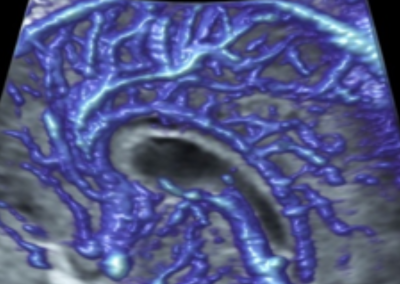

L’Université Paris Cité franchit une nouvelle étape dans le domaine de l’imagerie médicale anténatale avec l’acquisition d’un système d’Imagerie par Résonance Magnétique (IRM) 1,5T ARTIST™ de GE HealthCare. Cet équipement de pointe renforce les capacités de la Plateforme LUMIERE à l’hôpital Necker-Enfants malades, plateforme intégrée de soins, de recherche clinique et d’enseignement en imagerie médicale de la femme enceinte, du fœtus et du placenta.

L’acquisition de cette nouvelle IRM s’inscrit dans le cadre du protocole de recherche « LUMIERE SUR LE FETUS », dont les objectifs sont d’améliorer la prise en charge des pathologies anténatales, d’affiner leur pronostic et de contribuer à la réduction de la morbidité et de la mortalité à court, moyen et long terme. Cette acquisition a été rendue possible grâce au don exceptionnel de la Fondation LUMIERE d’un montant de 250k euros ainsi qu’au soutien de l’Université Paris Cité à hauteur de 670k euros.

Implantée à l’hôpital Necker-Enfants malades, la Plateforme LUMIERE est une plateforme unique au monde, qui a vu le jour grâce notamment au soutien de l’Université Paris Cité, de l’AP-HP et de la Fondation LUMIERE.

Une plateforme au service de la recherche et des patientes enceintes

Depuis 2020, la Plateforme LUMIERE offre aux femmes enceintes volontaires, entre 16 et 36 semaines d’aménorrhée et suivies à l’hôpital Necker-Enfants malades, la possibilité de participer activement à l’avancée de la recherche en médecine fœtale, tout en bénéficiant d’une IRM fœtale au cours de leur grossesse, réalisée dans un cadre sécurisé et encadré.

L’inclusion de ces patientes, depuis leur accueil jusqu’à la réalisation des examens d’imagerie, puis l’analyse des images et l’interprétation des résultats par des équipes expertes, enrichit une base de données structurée, unique au monde, au service de la recherche et de l’innovation en imagerie anténatale et en médecine fœtale.